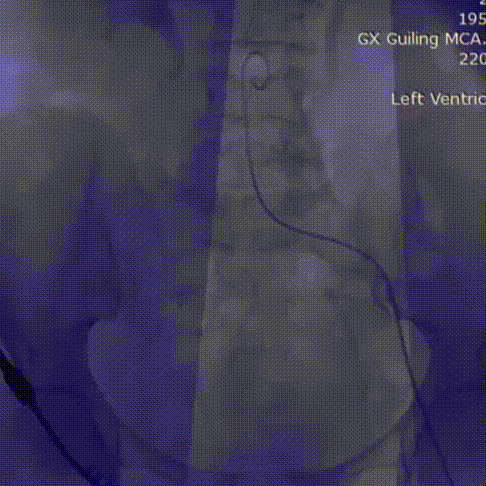

主动脉根部造影

23mm球囊预扩